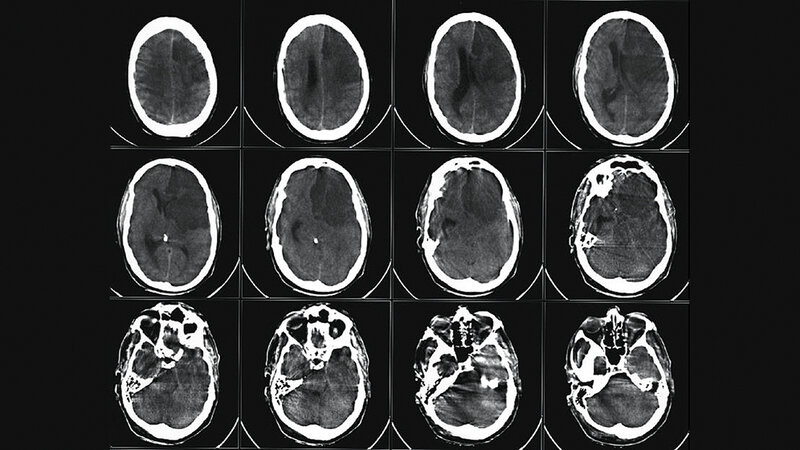

Die dritthäufigste Todesursache in Deutschland ist der Schlaganfall. Jedes Jahr sind Tausende Menschen davon betroffen. Zeit spielt bei diesem Thema die wichtigste Rolle überhaupt, denn es geht um nichts Geringeres als um das Gehirn des Menschen, dem Ursprungsort des Denkens, des Fühlens, der Persönlichkeit jedes Einzelnen. Symptome treten häufig unspezifisch auf, werden nicht rechtzeitig erkannt und mitunter unterschätzt. Hängende Mundwinkel, Wortfindungsstörungen, die Zeitung nicht richtig lesen können, sich komisch fühlen, plötzliche Kopfschmerzen oder für einen Moment nicht wissen, wo man sich befindet. Schon Minuten bis wenige Stunden nach Auftreten der ersten Symptome können bleibende Schäden zurückbleiben oder gar der Tod eintreten. Auf dem schnellsten Weg muss der Patient in eines der zertifizierten Krankenhäuser gebracht werden, um keine Zeit zu verlieren. Die Radiologische Diagnostik spielt eine immense Rolle. Deutschland ist mit etwa 350 zertifizierten Stroke Units flächendeckend gut aufgestellt, dennoch muss ständig an einer Verbesserung gearbeitet werden. Die Computertomografie ist bei den bildgebenden Verfahren noch die Untersuchungsmethode der ersten Wahl, da sie schnell verfügbar und von den meisten technischen Mitarbeitern bedient werden kann. Das MRT bietet hier zwar Vorteile in Bezug auf die Sensitivität, jedoch bilden die Liegezeiten, der Zustand des Patienten und die Erfahrung in der Auswertung und Bedienung, vor allem im Bereitschaftsdienst auf technischer und ärztlicher Ebene, große Hürden.